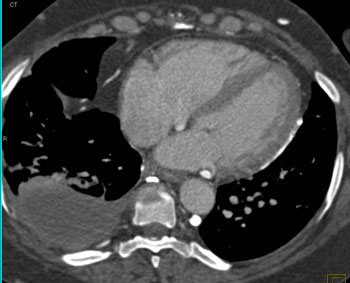

Question 18: In this patient with increasing dyspnea what is the best overall diagnosis?